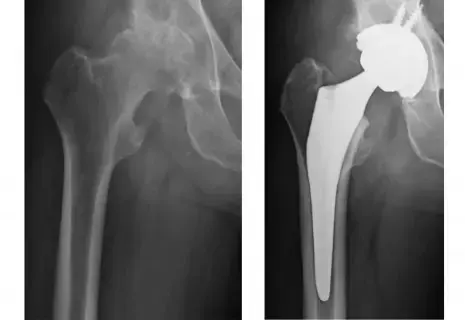

عملية استبدال مفصل في صنعاء: شاهد النتائج قبل وبعد

نستعرض في هذا التقرير كل ما يهمك معرفته عن عملية استبدال مفصل في صنعاء: شاهد النتائج قبل وبعد، يجري الدكتور محمد هطيف وفريقه ما معدله 5-6 عمليات استبدال مفاصل كبرى أسبوعياً في صنعاء. تظهر الفيديوهات الموثقة قدرة المرضى (حتى كبار السن) على المشي في اليوم التالي للعملية، مما يؤكد جودة المفاصل المستخدمة ودقة التقنية الجراحية.

شاهد: مريض يمشي بعد عملية استبدال مفصل الركبة

هذا الفيديو من داخل المستشفى في صنعاء يوضح سرعة التعافي بفضل الخبرة والدقة: